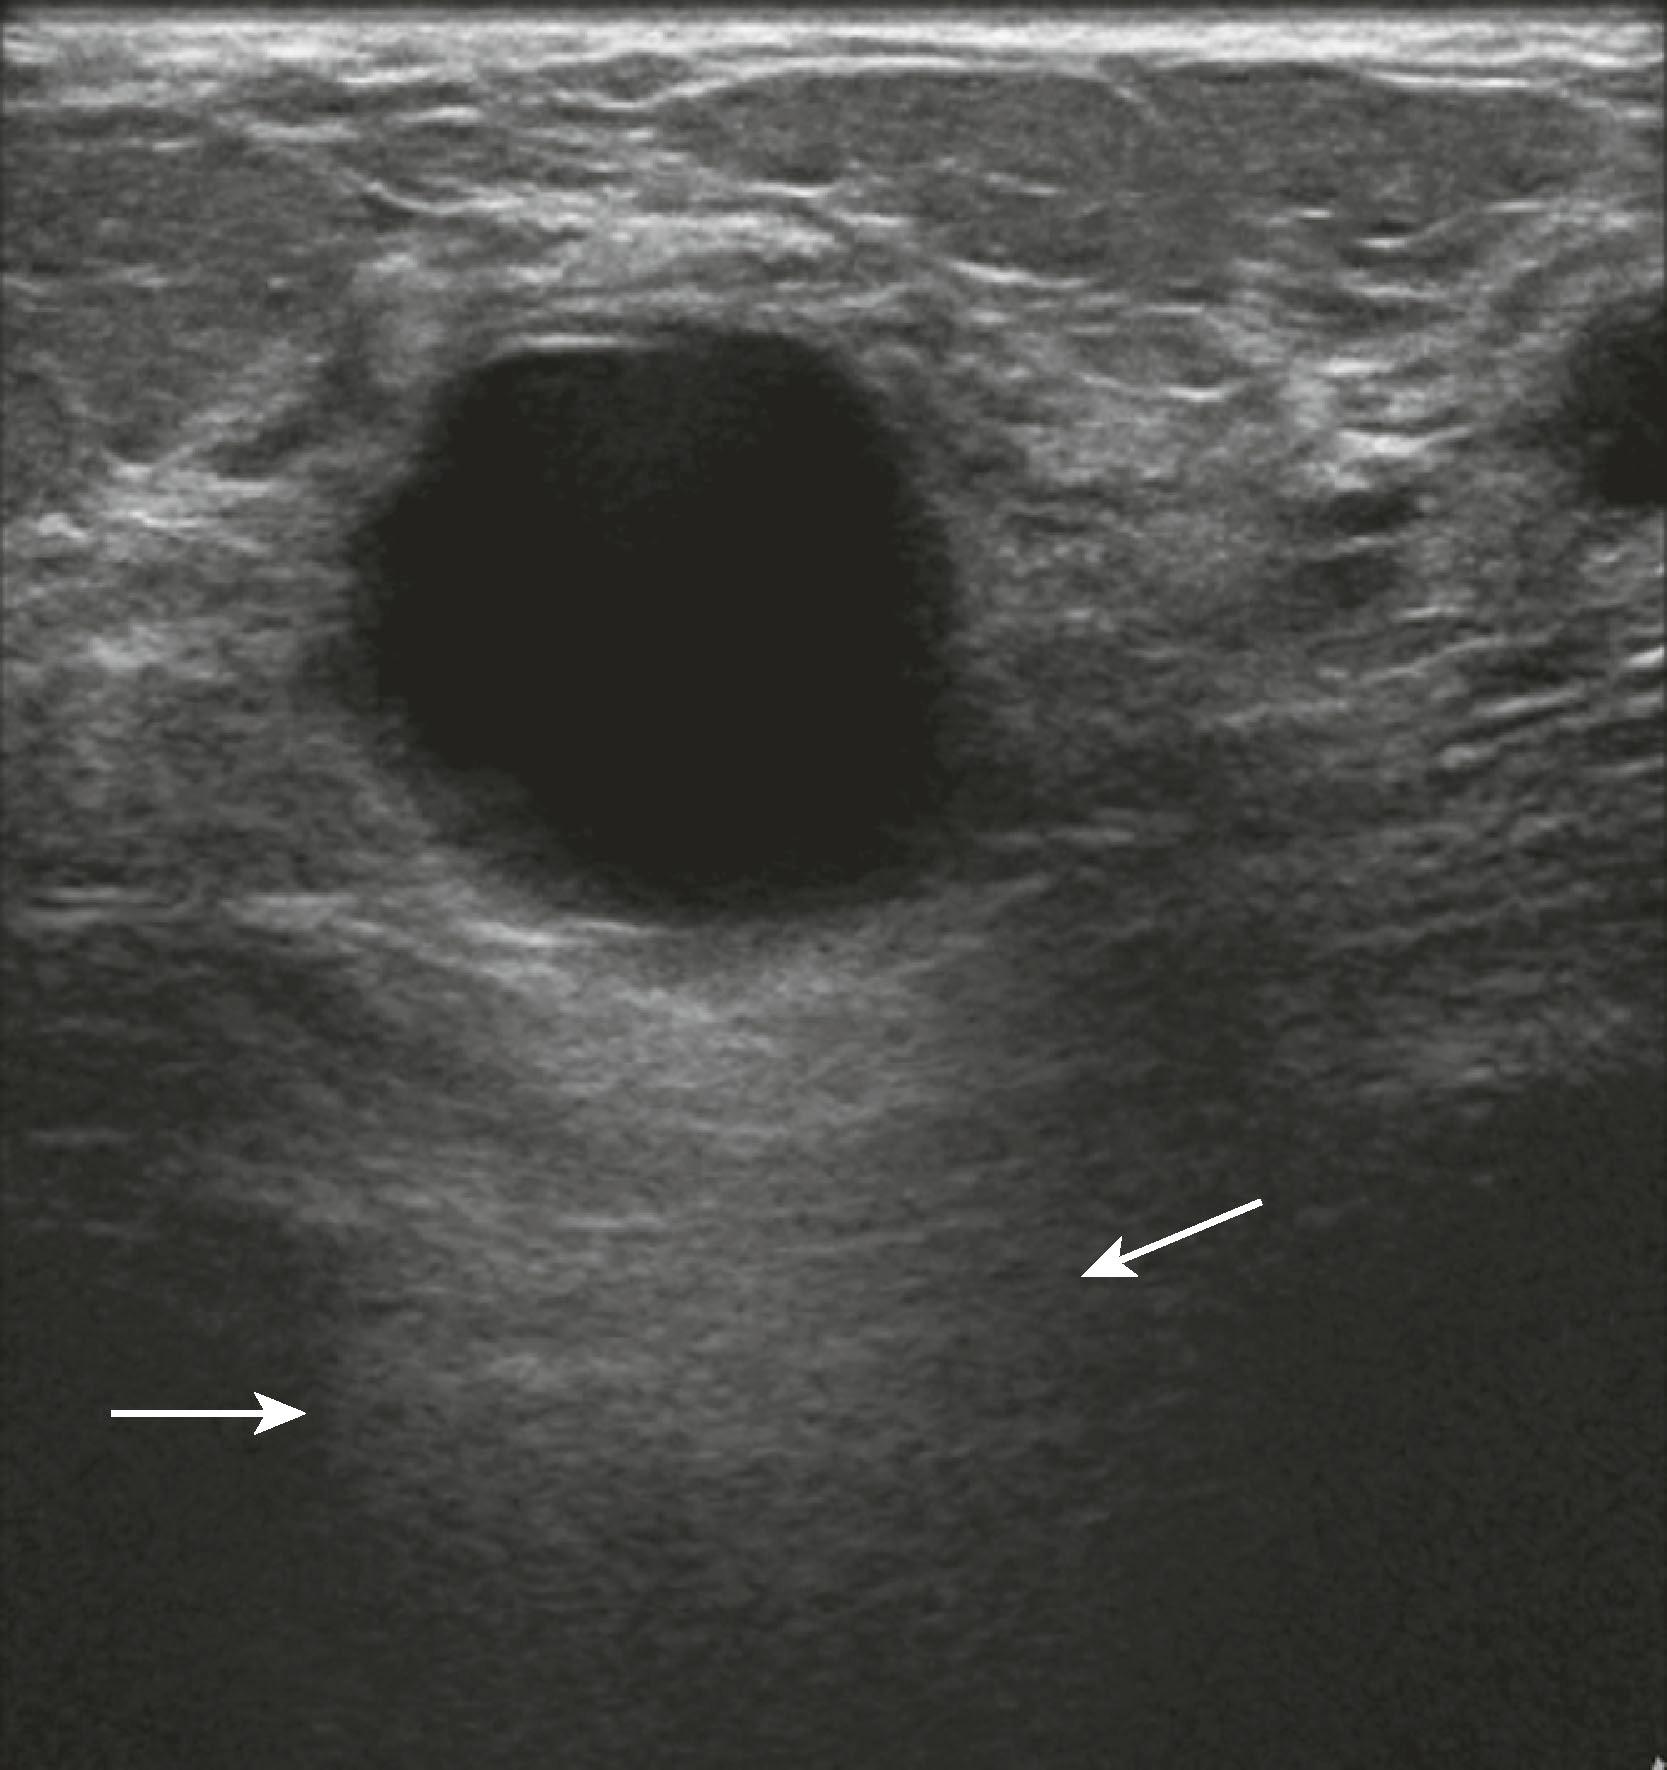

Sonographic features of simple cysts include well-defined margins, anechoic contents, and acoustic enhancement (increased sound transmission through the fluid compared with the surrounding tissue) ( Fig. 8.12 ). Simple cysts are rarely aspirated except for relief of patient symptoms, and the fluid obtained is often discarded rather than sent for cytological evaluation. However, some cysts contain internal echoes and are aspirated or undergo biopsy percutaneously to determine whether they are indeed complicated cysts or solid masses ( Fig. 8.13 ). The aspirate cytology of these complicated cysts does not always contain ductal epithelial cells, leading the pathologist to report the sample as suboptimal. A complex cyst (now referred to as a complex cystic and solid mass) is one that contains a mass or has complex internal architecture and will undergo biopsy of the noncystic portion, which may represent an intracystic papilloma or carcinoma ( Fig. 8.14 ).

Fig. 8.12, A simple cyst is anechoic (no internal echoes) because it is fluid filled and has no interfaces within, has smooth walls, and exhibits acoustic enhancement (arrows) owing to greater transmission of sound through fluid compared with adjacent tissue, where more sound is absorbed or reflected owing to the multiple interfaces in solid tissue.